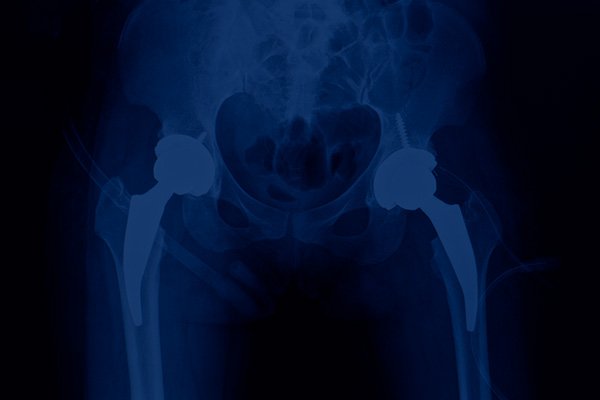

Artroplastia total do quadril

A artroplastia total do quadril trata casos graves de artrite, substituindo a cabeça femoral danificada por uma prótese fixada na bacia.

Artroplastia parcial do quadril

Essa cirurgia substitui apenas a parte danificada do quadril, sendo indicada para pacientes jovens com lesões localizadas.